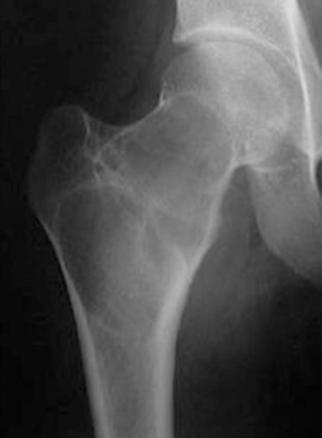

La lyse est cernée d'une sclérose périphérique régulière. Elle contient quelques travées qui sont régulières et respectées. L'ensemble dessinant un "contour géographique". Les corticales sont discrètement déformées et amincies, mais également de façon régulière, sans effraction. Il n'y a pas de réaction périostée. Il n'y a pas d'expansion apparente dans les parties molles. Cet aspect radiologique est calme, traduisant plutôt une tumeur bénigne. Ce processus est lent. Il reste donc régulier, souvent cerné d'une bande de sclérose qui est une construction réactionnelle de l'organisation, mais qui dans ce cas est bien limitée et respectée.